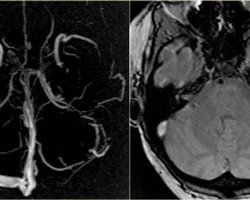

Думки Нетиповий тромбоз. Що це таке і чому ризик померти від нього менший, ніж від коронавірусу Семен Єсилевський